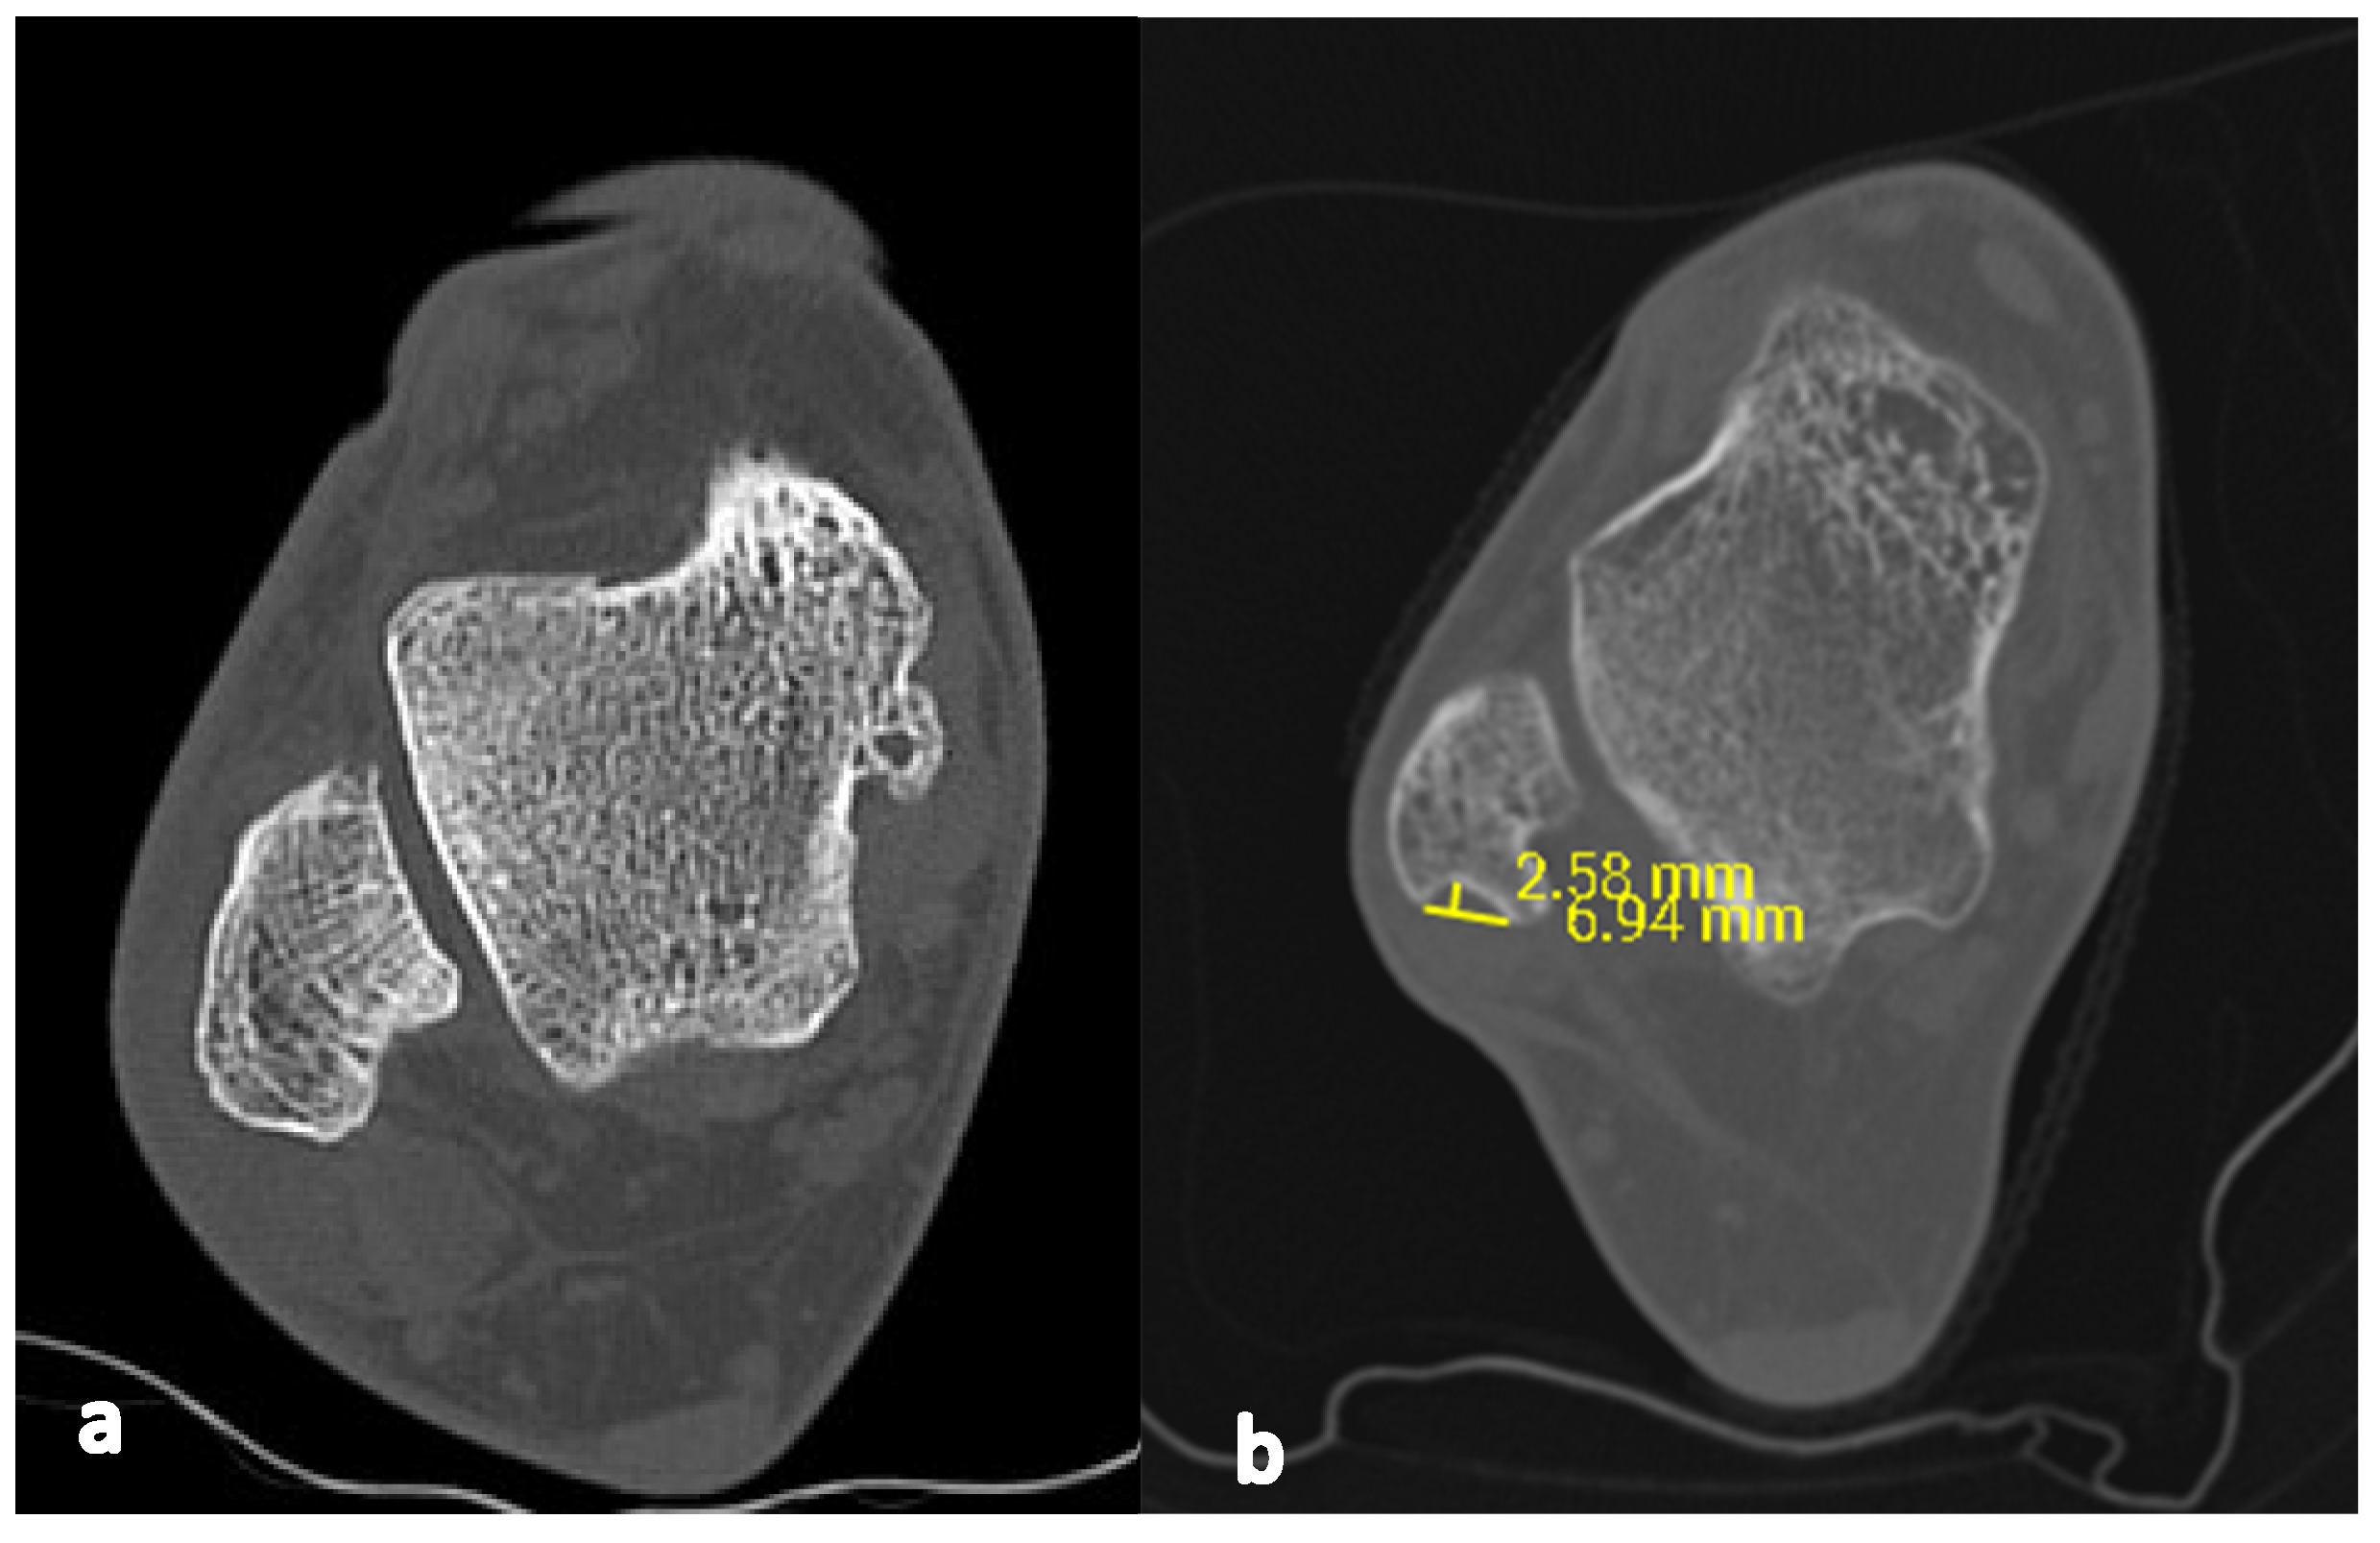

From radiopaedia.org

Image Groove Deepening Procedure This technique article describes a fibular groove deepening with preservation of the fibrocartilage in conjunction with repair of the superior peroneal retinaculum. Indications and contraindications of endoscopic retrofibular groove deepening for management of type a intrasheath peroneal. Modified fibular groove deepening combined with superior peroneal retinaculum repair for treating peroneal tendon subluxation. 15 adachi reported that the. Simple repair of. Groove Deepening Procedure.